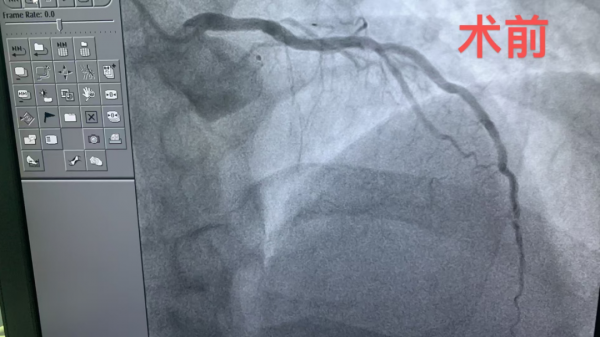

1、39歲男性,前降支閉塞,行血栓抽吸+冠脈內溶栓。

2、71歲男性,右冠閉塞,行藥物球囊擴張成形術。

3、69歲男性,雙支病變,行介入治療。